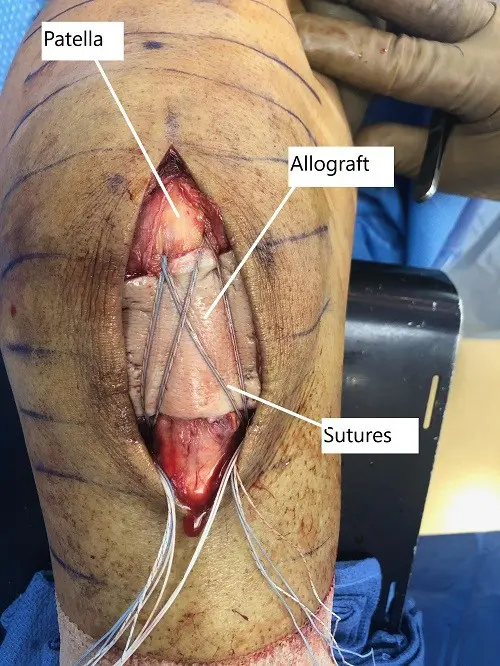

A 2 mm fiber tape x4 was used to put Krackow suture, one on either side on the proximal and distal end of the patellar. The tails of the sutures were in the midline. Now, the lower wall of the patellar was exposed, posterior to the patellar side. It was cleaned with the use of curette and Bovie. The bone was decorticated and two drill holes were done and planning for suture anchors.

Four drill suture anchors were brought on either side of the patellar, posterior to the patellar tendon. The sutures were brought to the front through the patellar tendon and reticulum using a suture passer.

Once they were brought up, the tails of the suture in the midsubstance of the patella were tied to each other using four knots separately. The knots were buried and cut. An Arthroflex was opened. It was put on the patellar tendon and sealed proximally.

The distal one-third of the graft was removed and little of access. The allograft was found to cover the patellar tendon and is to eternity. Now the two sutures from each side of the suture anchors proximal were crossed, one set was crossed and one set was taken straightening, put in the tibia lateral to the tibial tuberosity using SwiveLock on either side. Excellent configuration was achieved.

Intraoperative image showing the repaired patellar tendon with overlying allograft

The knee was flexed in 30 degrees at that time. Then the patellar tendon repair was stopped. The allograft was posterior to the sutures opposing to the patellar tendon repair in the patellar tendon. The wound was again washed.

The patellar retinaculum was repaired on either side using #2 FiberWire. The sutures and towards the center of the patellar retinaculum were incorporated into the Arthroflex graft.